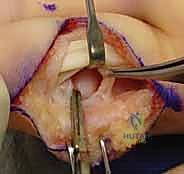

1. الرد المفتوح والتثبيت الداخلي (ORIF)

هذه هي الجراحة الكلاسيكية والمفضلة عندما يكون هناك قطعة عظمية واحدة كبيرة يمكن تثبيتها.

* الخطوات: يقوم الدكتور هطيف بعمل شق جراحي دقيق (عادة على شكل متعرج Bruner incision) للوصول إلى المفصل دون إتلاف الأوتار. يتم إرجاع العظم المكسور إلى مكانه التشريحي بدقة مجهرية.

* التثبيت: يتم تثبيت الكسر باستخدام مسامير تيتانيوم متناهية الصغر (Mini-screws بحجم 1.3 مم أو 1.5 مم) أو باستخدام أسلاك كيرشنر (K-wires). يضمن هذا التثبيت الصلب قدرة المريض على بدء تحريك إصبعه بعد أيام قليلة من الجراحة.